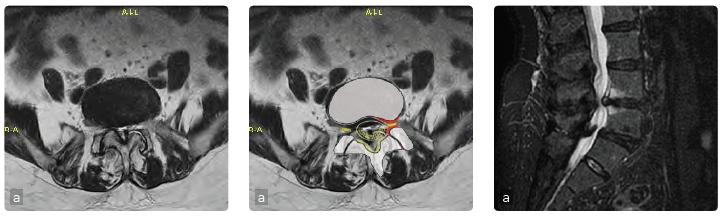

Caso 3: Stenosi lombare

Femmina, 70 anni, stenosi lombare. Lombosciatalgia da 2 anni resistente alla terapia antalgica. Radicolopatia compressiva di L3 a sinistra con iniziale deficit di forza del quadricipite. La RMN dimostra una stenosi grave multilivello (a). L'intervento è consistito nella decompressione mediante laminectomia e rimozione del legamento giallo ossificato (b) e artrodesi L3-L5 (c), lo spazio L4-L5 è stato stabilizzato anche anteriormente. Ottimo il recupero funzionale della forza e miglioramento del dolore a 3 mesi.